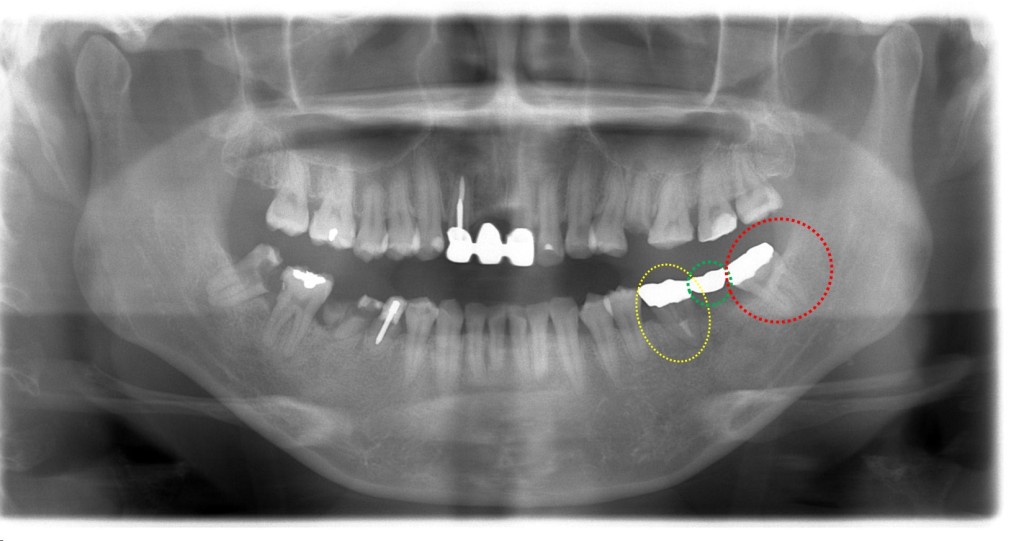

下写真は3か月後のレントゲン写真になります。

移植後、経過良好で赤〇(親知らず)を使ってブリッジが装着されました。